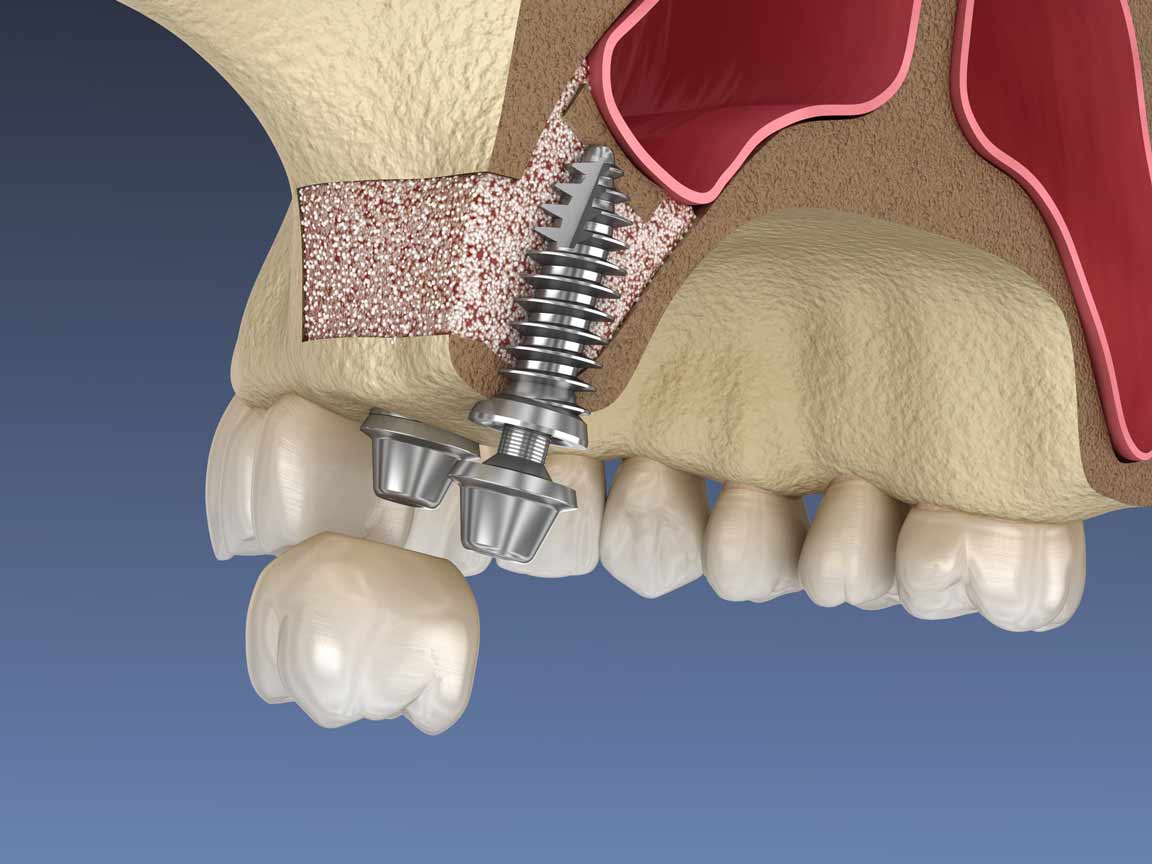

پیوند استخوان در فک دارای شیوه های مختلفی است. برای افزایش طول استخوان برای فک بالا، عمدتاً از روش سینوس لیفت استفاده میشود. در این روش، پس از تحلیل یا کاهش ارتفاع استخوان، سینوسها برای فراهم کردن فضای لازم به سمت پایین میآیند. سپس با استفاده از تکنیک سینوس لیفت، سینوسها به بالا برده شده و با پودر استخوان، فضای خالی بین آنها پر میشود. برای افزایش عرض استخوان نیز میتوان از روش ریج اسپلیت بهره گرفت. این روش، اگرچه در همه جا قابل اجرا نیست، اما میتواند به بهبود عملکرد ایمپلنت کمک کند. لازم به ذکر است که هر دو روش نیازمند دقت و مهارت بالای جراحی است و باید توسط یک جراح متخصص اجرا شود.

پیوند استخوان فک همراه با سینوس لیفت

پیوند استخوان فک همراه با سینوس لیفت

پیوند استخوان به دو شکل میتواند انجام شود؛ همزمان با نصب ایمپلنت یا به صورت جداگانه. در شرایط خاصی، پزشک ممکن است تصمیم بگیرد که از پودر استخوان در جریان عمل جراحی ایمپلنت استفاده کند. این رویکرد، به پیوند بهتر استخوان با ایمپلنت کمک میکند و افزایش استحکام و پایداری ایمپلنت را به همراه دارد. اما در برخی موارد دیگر، ممکن است استخوان مورد نیاز برای پیوند، به میزان زیادی تحلیل یافته باشد. در این شرایط، عمل جراحی پیوند استخوان به صورت مجزا انجام میشود. این روش معمولاً در مواردی که نیاز به افزایش طول یا عرض استخوان وجود دارد، مورد استفاده قرار میگیرد. بنابراین، انتخاب روش مناسب برای پیوند استخوان، بستگی به شرایط خاص هر بیمار و تشخیص پزشک دارد.